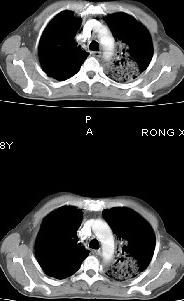

男68岁,反复发热、咳嗽,咯痰1月,曾有咯血史,双肺闻及呼吸音增粗。

左肺上叶尖后段及下叶多发实变阴影,内见支气管充气征,段以上支气管尚通畅,肺门区未见软组织肿块影,结合病人有反复发热病史,首先考虑感染性病变(干酪性肺炎不能排除),建议抗炎治疗后复查或结合纤支镜检查。

左肺上叶尖段及下叶干酪性肺炎可能性大,建议结合临床相关检查.右肺中叶炎症.建议治疗后复查.

该患者在25天前外圆平片见右肺中上肺野大片状影,(治疗不祥,在反复问病史后患者告诉;近一月住在新房内,搞装修),我认为首先考虑是感染,而且过敏性肺炎可能性大。

右下中央型肺癌伴阻塞性肺炎!

结果是过敏性肺炎,谢谢,楼主!